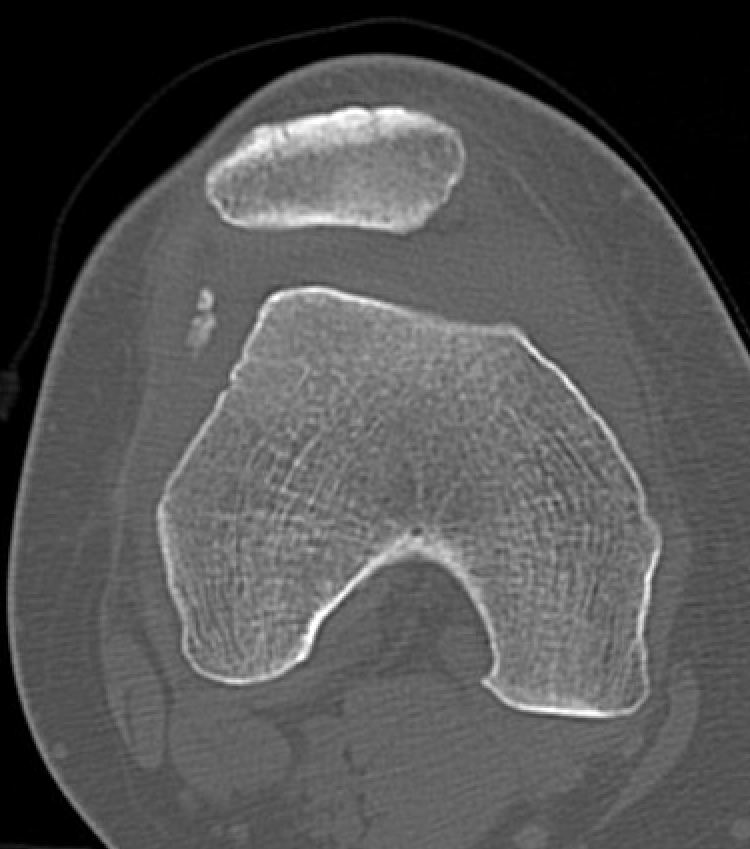

CT

Osteochondral fracture of the lateral femoral condyle

Large osteochondral fracture medial facet patella

Large osteochondral fracture lateral femoral condyle